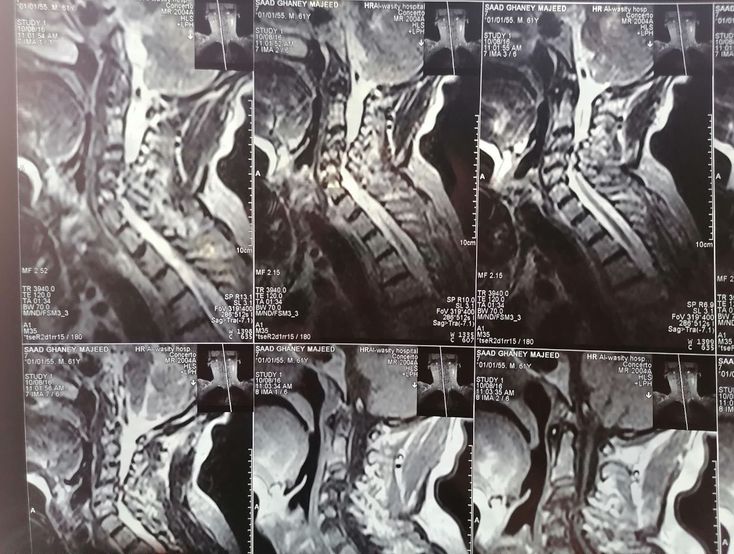

Spinal cord

Can anyone tell me what this condition is !!!đđŋ

Spinal cord compression